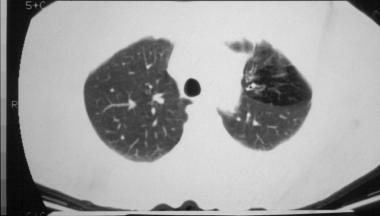

中度或晚期时的肺部可能出现线状阴影和散在结节,并可能观察到节段性、斑片性或小叶性肺不张,儿童比成人更为多见,通常表现在右上叶。

图3 囊性纤维化患者双侧支气管扩张,并伴有左上叶肺不张

图4 右肺完全不张伴支气管扩张,注意左肺过度充气